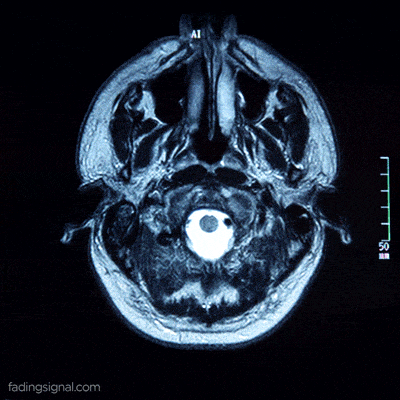

2007年《柳叶刀》报道的那位法国男子,虽然脑室急剧扩张,但这实际上是慢性脑积水造成的物理压缩。

他的大脑皮层并未消失,而是被压成了一层薄纸贴在颅骨上(下图),如同被压扁的三明治,结构依然完整,神经连接依然存在。这证明的是大脑惊人的可塑性。

图源:柳叶刀